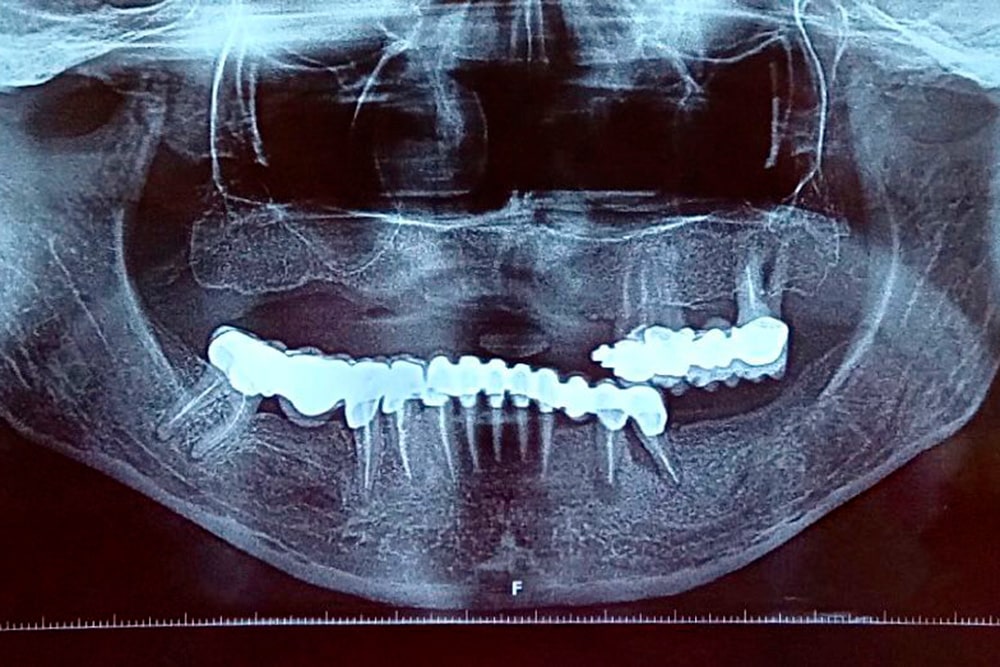

În urma anamnezei și a investigațiilor suplimentare paraclinice (ortopantomogtafie si CBCT), am decis reabilitarea orală complexă cu ajutorul implanturilor și a lucrărilor fixe.

În radiografia de mai jos se poate vedea lucrarea finală efectuată cu succes de către colegii noștri